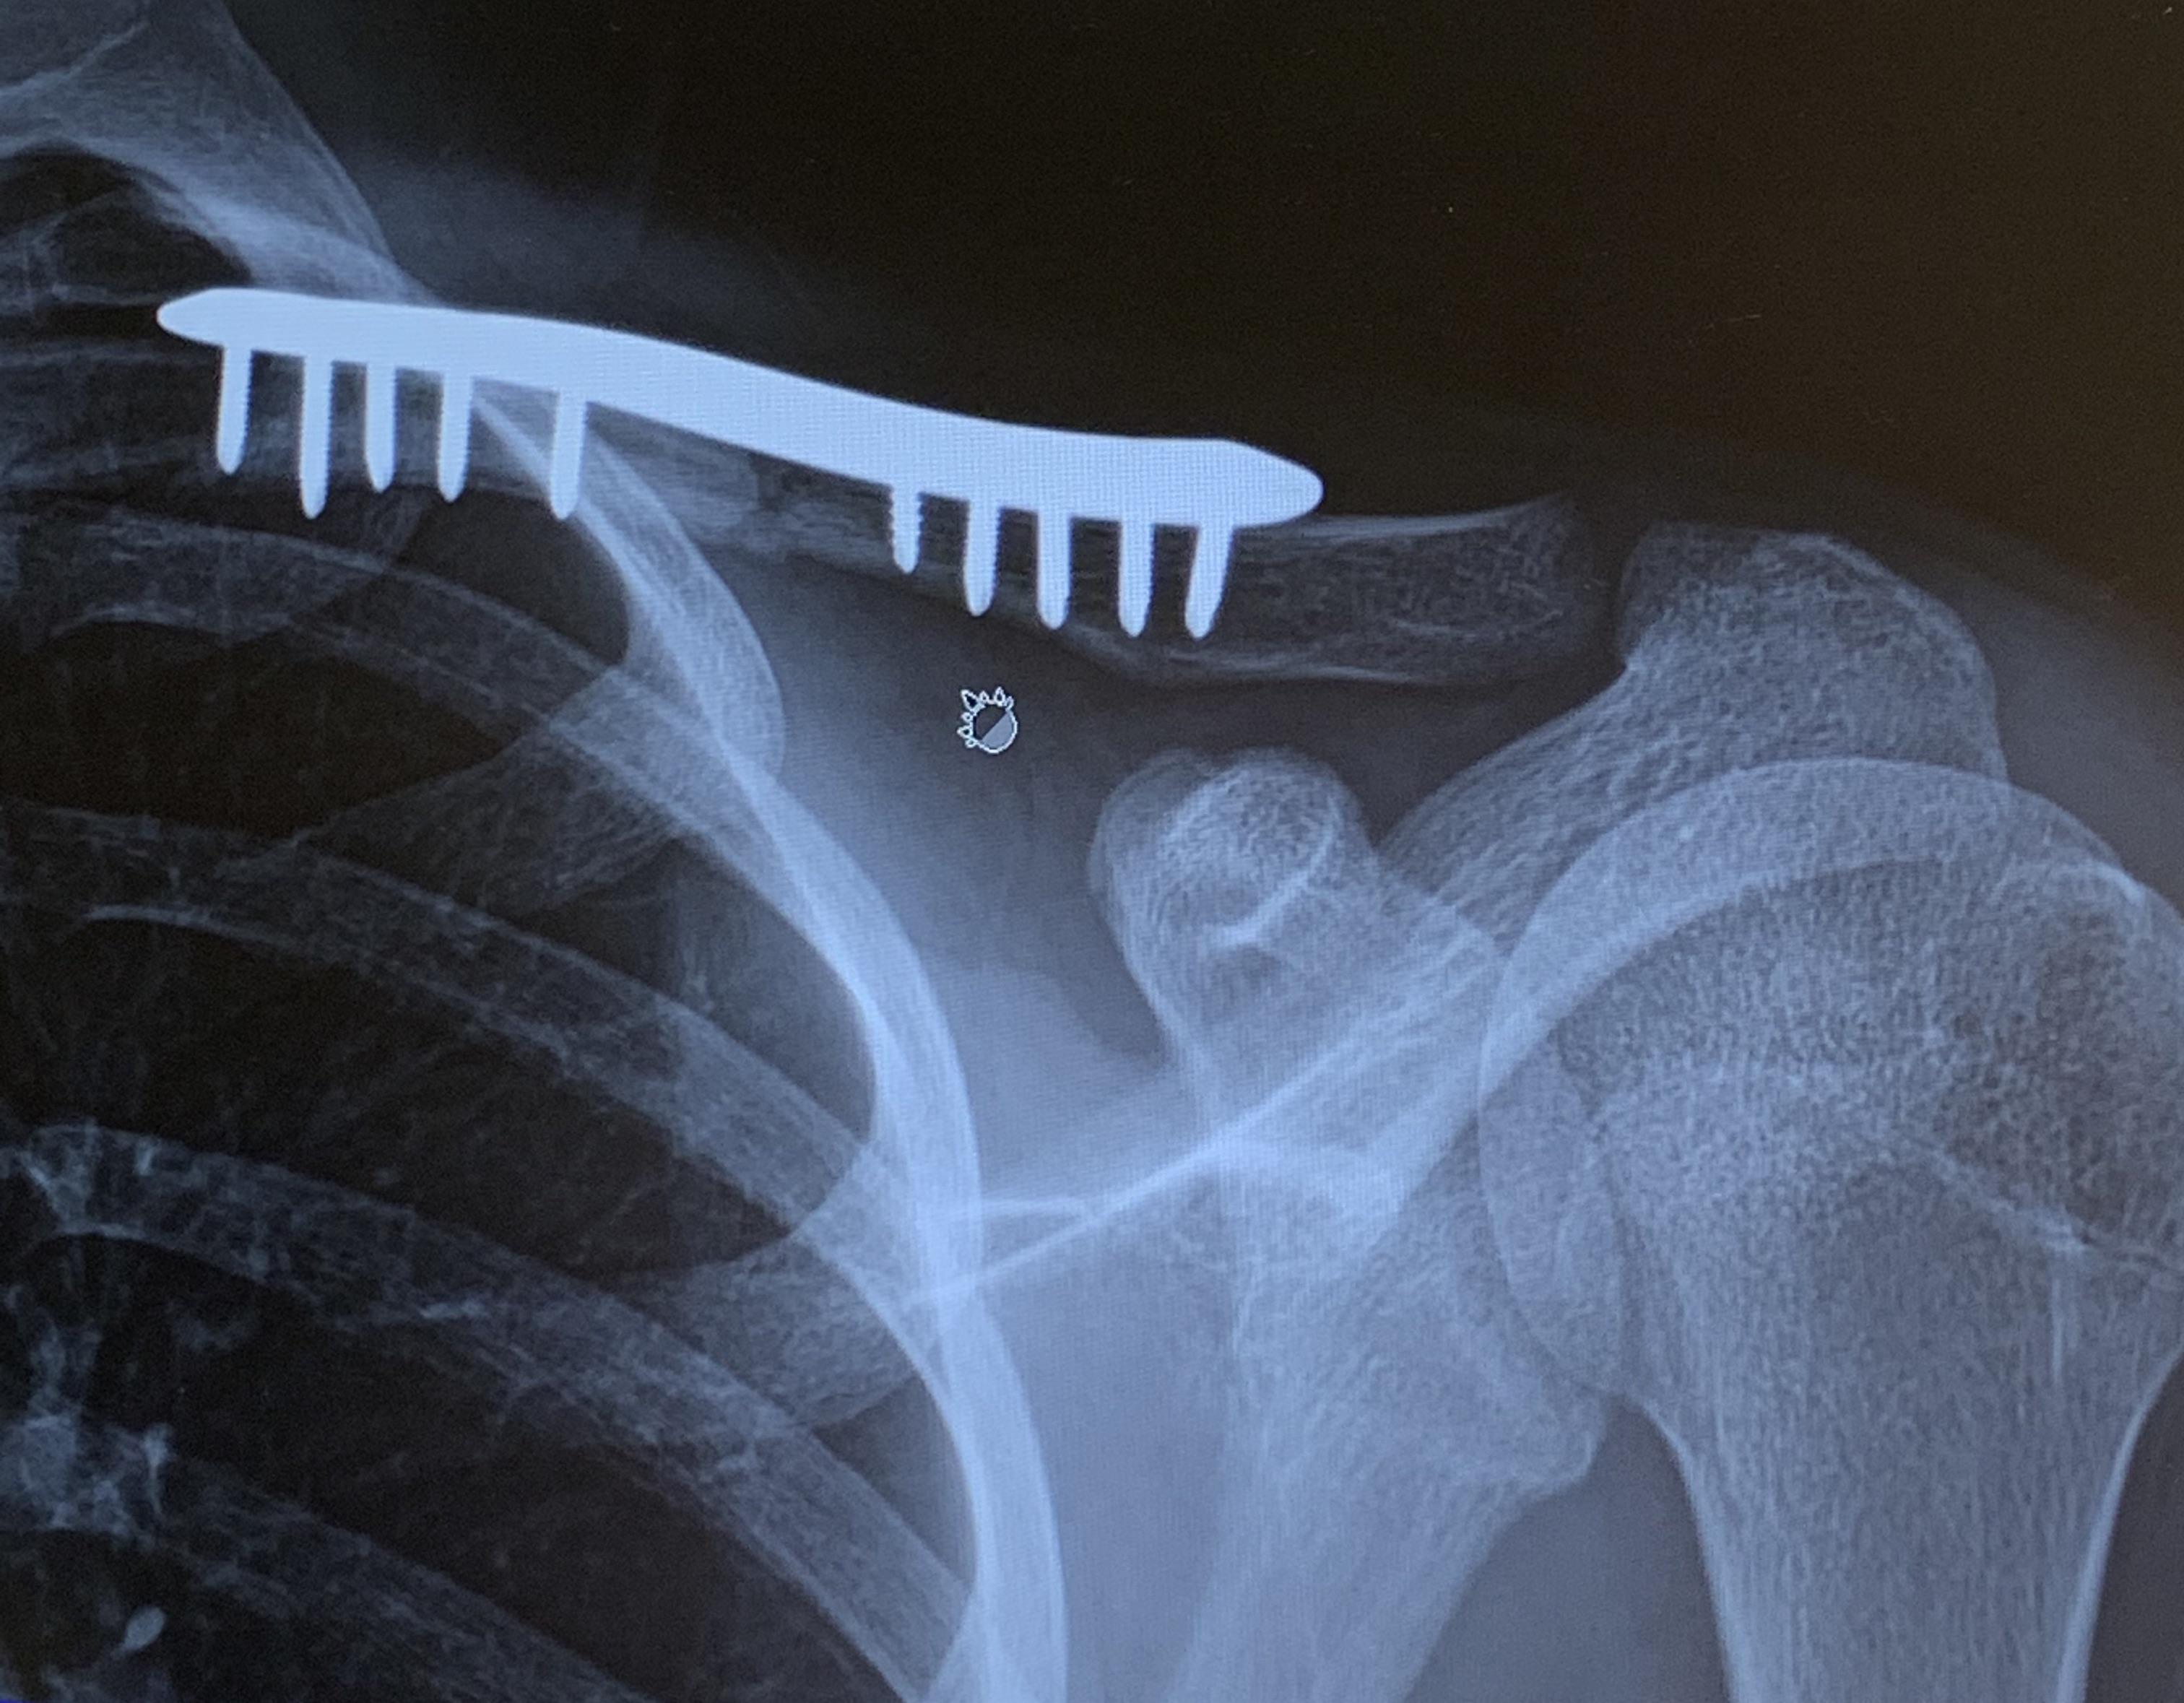

From www.reddit.com

XRay of my collarbone postsurgery pics How Much Does Collarbone Surgery Cost Find out when you might need orif, what to expect before, during and after. Learn about open reduction and internal fixation (orif), a type of surgery to stabilize and heal a broken collarbone (clavicle). Learn about the causes, symptoms, and treatment options for clavicle fractures, or broken collarbones. Knee replacements in singapore public hospitals cost an average of $5,000 to. How Much Does Collarbone Surgery Cost.